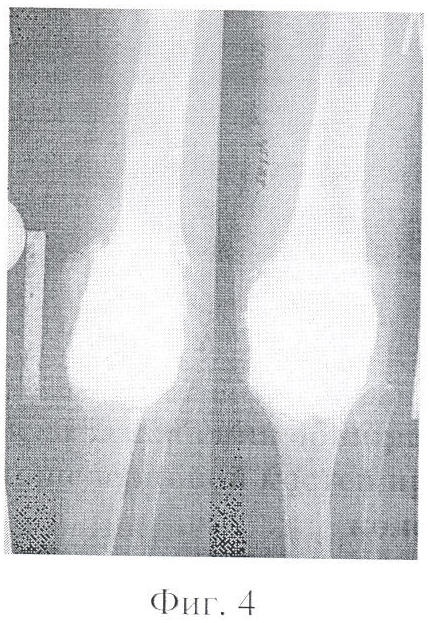

Фигура 4 – установка цементного спейсера после удаления эндопротеза «Феникс» в результате позднего нагноения протезированного левого коленного сустава (2004 г.).

В мае 2004 года по поводу позднего нагноения выполнена операция: удаление эндопротеза, санация сустава, установка цементного спейсера (фиг.4).